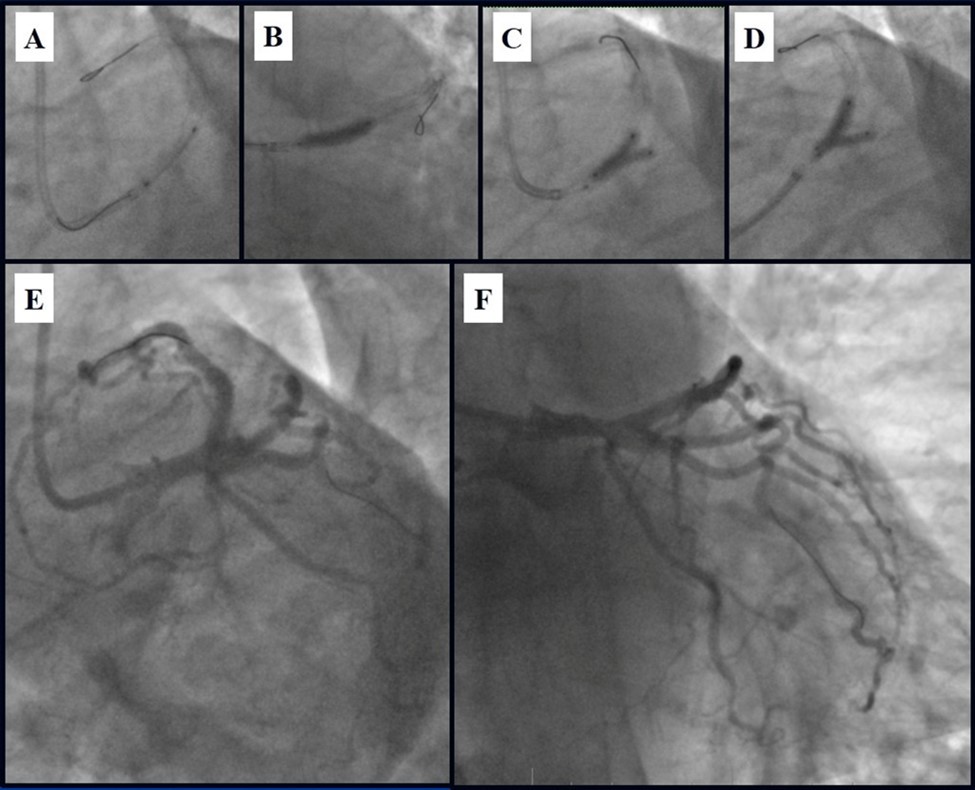

Due to financial problems the second stage was performed after 3 months (during this time the patient solved his financial problems). CAG revealed patent stents in LAD (Figure 7), and 60-70% restenosis by BMS in RCA (Figure 8). In-stent restenosis was treated by plain old balloon angioplasty (POBA), the optimal result was obtained (Figure 9). After LMCA quadrifurcation balloon predilation, 2.5×26 mm DES (Resolute Integrity, Medtronic) was implanted in the IMA, using a modified balloon mini-crush technique. The stent was minimally protruded in the LMCA and its edge was crushed by preloaded MB balloon. Next 2.5×30 mm DES (Resolute Integrity, Medtronic) was implanted in OM1 through the CX (first marginal and circumflex arteries in this particular case have the same ostium). The stent was protruded in the LMCA as in conventional modified balloon crush stenting technique, after stent deployment, its balloon was pulled back and overinflated, then protruded stent was crushed by preloaded MB balloon (Figure 10). 3.5×15 mm DES was implanted in the LMCA so that distal part of the stent covered ostial and proximal segments of the LAD. Sequential post-dilatations were performed using a kissing balloon technique (1. LMCA-LAD-IMA,2. LMCA-LAD-CX-1OM). After post-dilatations, through the stent implanted in CX-OM1, coronary wire and smaller diameter balloon (2.0 mm) were advanced in direction of the CX mid-segment and by balloon dilatation stent’s strut was opened (provisional stenting technique for CX). Finally, the proximal optimization technique was performed in the LMCA using a 3.5 mm diameter non-compliant balloon (Figure 11). The final angiographic image was good, the intervention ended without complications (Figure 11, Figure 12). We could not confirm the result with IVUS or OCT due to several technical and financial problems (not covered by insurance). 1 month after PCI, at regular checkout, the ejection fraction was 48%, the functional class of the Congestive Heart Failure decreased from class II-III to class I and the patient complaints have been disappeared.

Figure 11.Stenting of the LMCA quadrifurcation: A, B – Stenting of the LMCA; C –Kissing balloon post dilatation of the IMA-LMCA-LAD; D - Kissing balloon post dilatation of the CX-OM1-LMCA; E, F - angiography result.